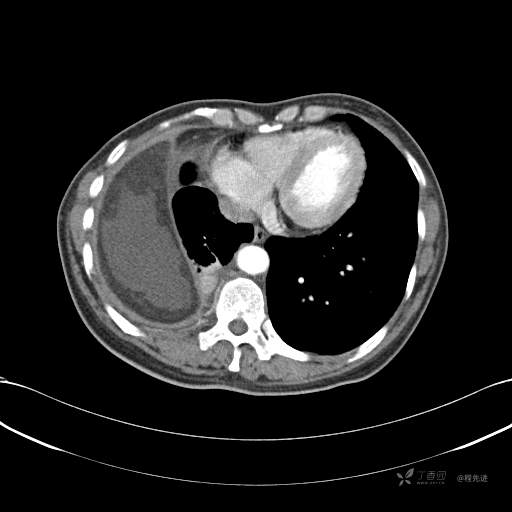

患者性别:女

患者年龄:51岁

简要病史:胸闷半年

肺淋巴管肌瘤病 (7)

乳糜胸 (8)